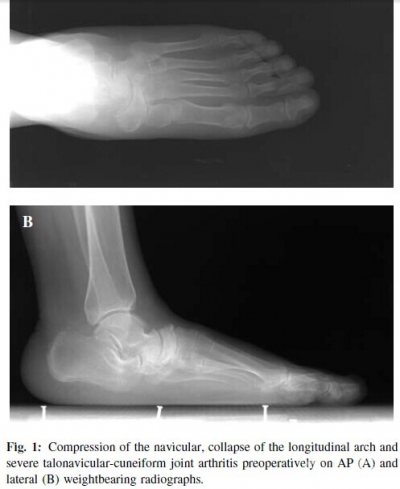

In the absence of a satisfactory response to conservative measures for more than 6 months, nine Stage III MWD patients (four male and five female), with an average age of 48.2 (range, 41 to 58) years, underwent perinavicular arthrodesis with reverse “V”shaped osteotomy and autologous iliac bone graft between 2006 and 2008. The mean followup time for radiological and clinical evaluation was 22.4 (range, 12 to 52) months. All patients complained of midfoot pain on standing and walking and had gradual collapse of the medical longitudinal arch without history of trauma or glucocorticoid use or secondary osteonecrosis from rheumatoid arthritis, diabetes, tuberculosis, etc. The compression of the navicular, collapse of the medical longitudinal arch and severe talonavicular·cuneiform joint arthritis were found in all cases on radiography (Figure 1).

At the last followup, all feet were pain·free, and the deformity was also corrected satisfactorily without any surgical complication including infection, skin necrosis, and nerve injury. There was no case of persistent graft donor site pain at the hip. The average AOFAS ankle·hindfoot score was improved from 40.1±8.3 preoperatively to 90.9±2.1 at the last followup (p = 0.0004).Radiographically, all the feet fused solidly at 3 months after surgery without screw breakage or loosening (Figure 5).The foot appearance improved with normal longitudinal arch height on the lateral view (Figure 6). The average longitudinal arch height increased from 46.1± 2.1mm preoperatively to 53.5±2.3 mm at the last followup (p < 0.05) on the lateral weightbearing radiograph.